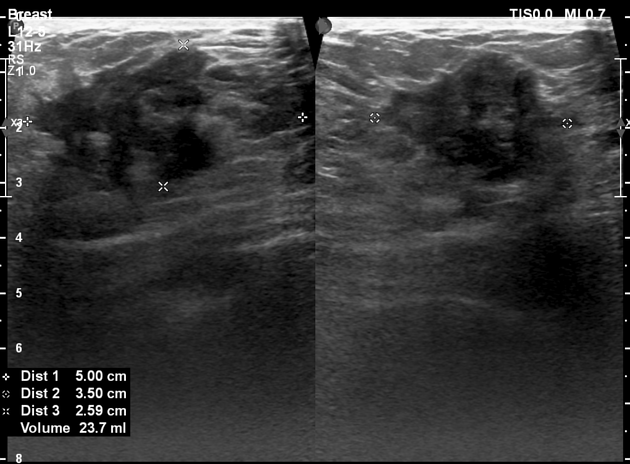

در سونوگرافی پستان، BI-RADS بر اساس ویژگیهای ظاهری ضایعات مانند شکل، حاشیه، یکنواختی، اکوژنیسیته و وجود یا عدم وجود سایه خلفی تعیین میشود.